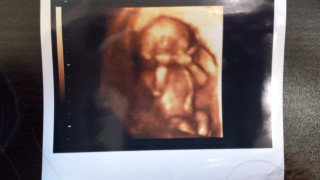

今のところ全部カメラ目線の エコーばかりです!

このエコーは、私方お父さん(おじいちゃん)に似てるみたい!?

とーっても可愛くて毎日エコー写真見てニヤニヤ!

性別も男の子と言われましたヽ(^o^)丿

やっと人間らしい元気な姿が見れて嬉しいです。

CRLは10㎝です。